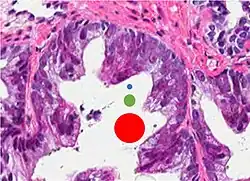

Intraductal carcinoma of the prostate with an infiltrative growth pattern may be morphologically difficult to distinguish from invasive cancer. One focus shows comedonecrosis (arrow), morphologically suggesting Gleason pattern 5 invasive carcinoma (a haematoxylin and eosin, b CK5/6)[20] -